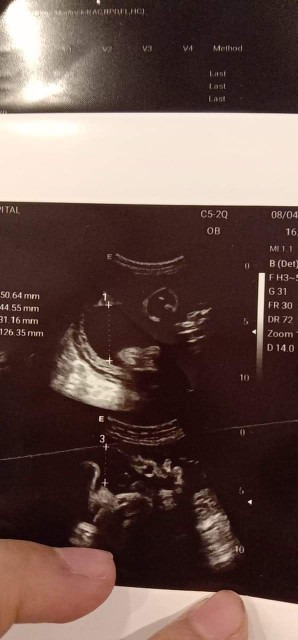

หญิงไหมคะแบบนี้...32wท้องเเรก อยากได้หญิง😁😁😘😘 ขอดูผลซาวด์ของแม่ๆหน่อยจ้า #ขอบคุณล่วงหน้านะคะ

หน้าจะ ญ .ของเค้า ญ 34สัปดา

น่าจะผู้หญิงนะคะ

บ้านนี้หญิงจร้า